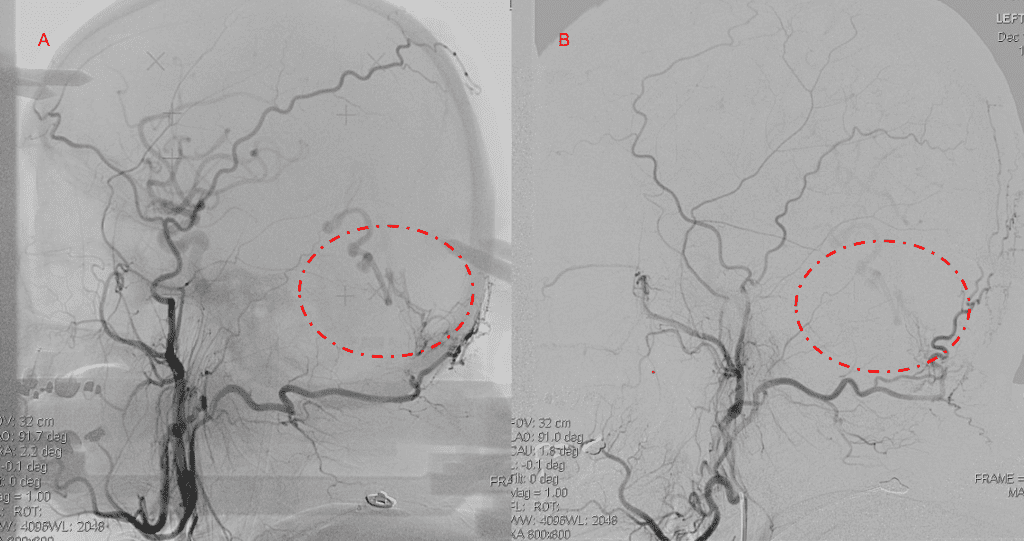

Figure 5. Bilateral ECA Lateral angiograms (A and B) demonstrates small residual indirect supply To the AVM from the bilateral Occipital arteries.